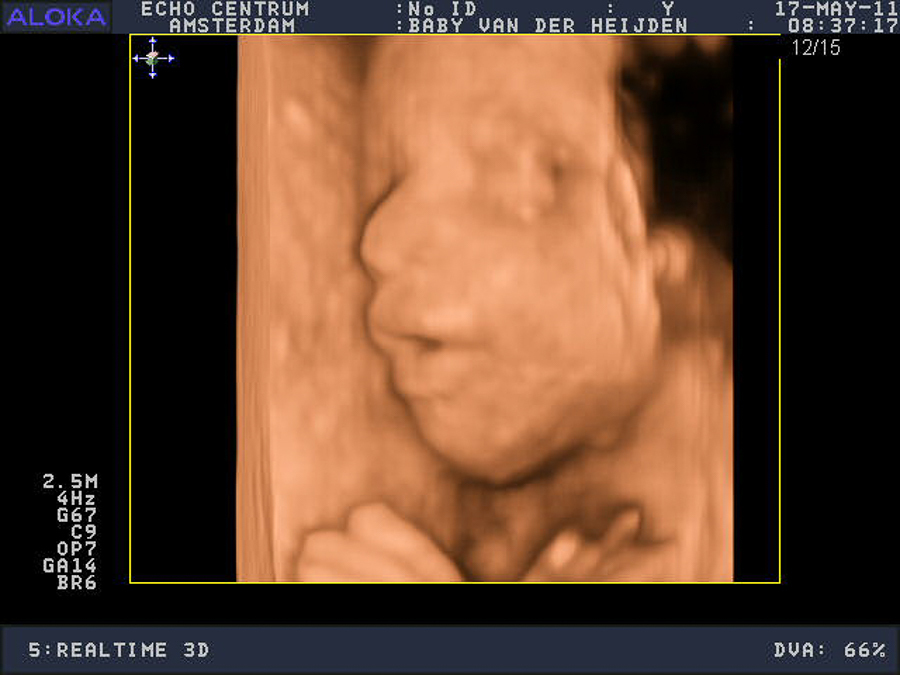

You can also choose to have an extra ultrasound simply to see your baby again — this is called a non-medical (fun) ultrasound or “pretecho.” Some parents choose this to find out the baby’s sex, or just to enjoy that special moment together.

Would you like an extra ultrasound just for fun, without a medical reason? That’s called a “fun scan” and costs €55. You can call or email our assistant to schedule one.

• Fun scan – just to admire your baby (between 8–39 weeks)

Because ultrasounds are not harmful to you or your baby, you can have as many as you like if it makes you feel more comfortable.